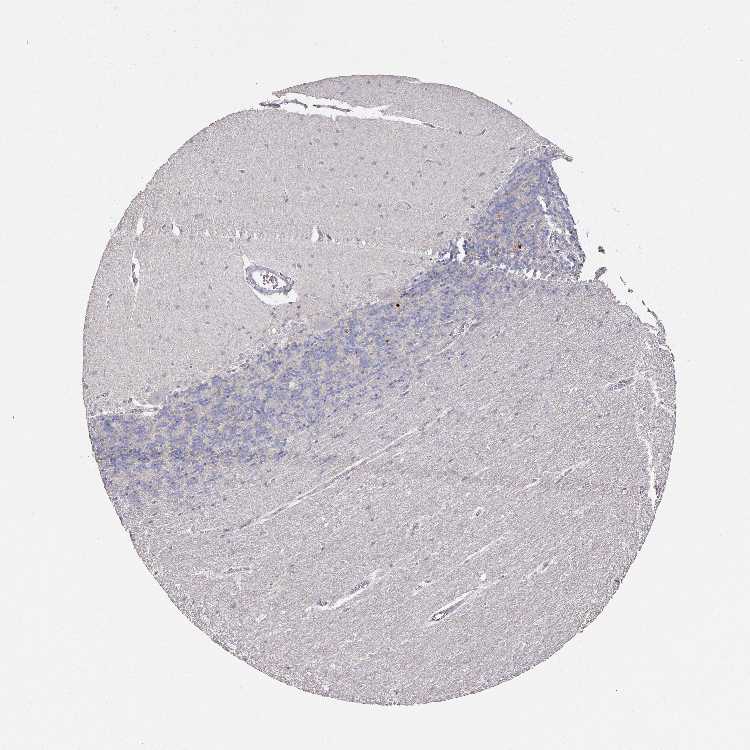

CEREBELLUM - Antibody stainingi

Antibody staining in the annotated cell types in the current human tissue is reported as not detected, low, medium, or high, based on conventional immunohistochemistry profiling in selected tissues. This score is based on the combination of the staining intensity and fraction of stained cells.

Each image is clickable and will lead to virtual microscopy that enables deeper exploration of all samples and also displays staining intensity scores, fraction scores and subcellular localization as well as patient and tissue information for each sample.

Antibody HPA029874Antibody CAB015949Antibody CAB016522

Purkinje cells Not detectedNot detectedMedium

Cells in granular layer Not detectedNot detectedNot detected

Cells in molecular layer Not detectedNot detectedNot detected